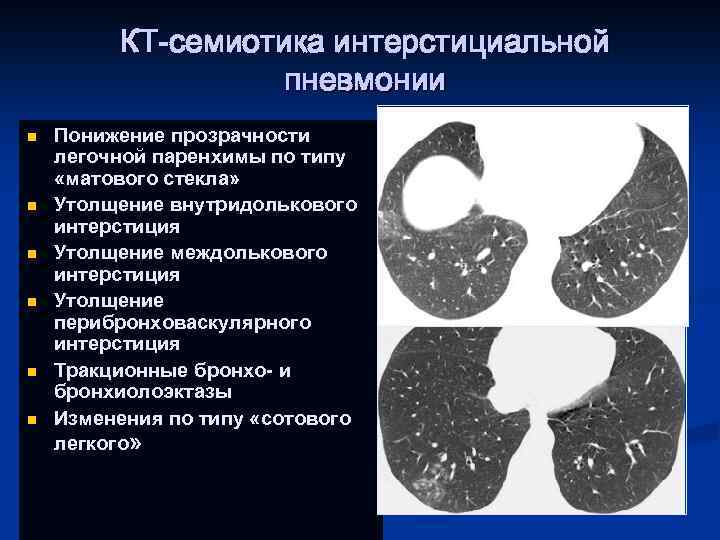

КТ-семиотика интерстициальной пневмонии n n n Понижение прозрачности легочной паренхимы по типу «матового стекла» Утолщение внутридолькового интерстиция Утолщение междолькового интерстиция Утолщение перибронховаскулярного интерстиция Тракционные бронхо- и бронхиолоэктазы Изменения по типу «сотового легкого»